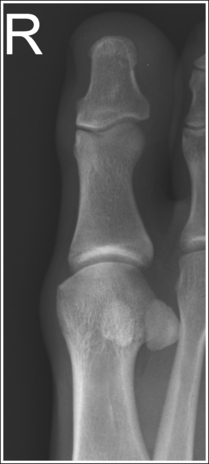

See Figures 6-8 and 6-9 and Box 6-4.

FIGURE 6-8 First lateral toe projection with accurate positioning. DIP, Distal interphalangeal; MTP, metatarsophalangeal.

FIGURE 6-9 Second lateral toe projection with accurate positioning. DIP, Distal interphalangeal; MTP, metatarsophalangeal; PIP, proximal interphalangeal.

The digit is demonstrated in a lateral projection. The posterior surface of the proximal phalanx demonstrates more concavity than the anterior surface, and the condyles are superimposed. The soft tissue outline of the nail, when shown, is in profile anteriorly.